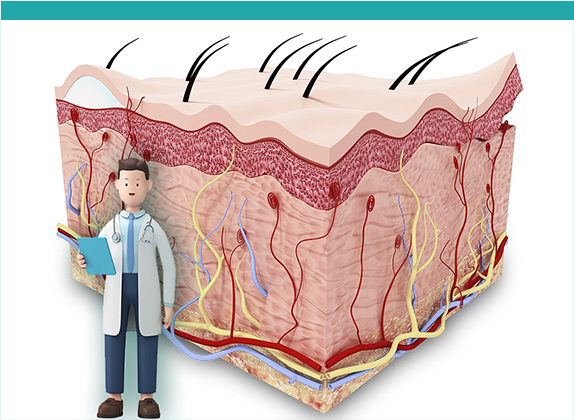

種髮係咩? 種髮其實係將你後枕部健康嘅毛囊移植到脫髮嘅位置,等嗰度可以重新生頭髮。後枕部嘅毛囊通常唔受荷爾蒙影響,所以移植之後都可以保持健康生長,效果自然又持久。